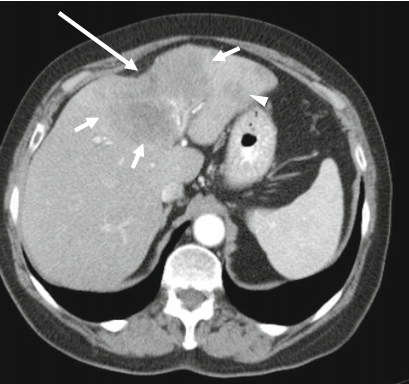

肝转移瘤可引起肝包膜凹陷,尤其见于原发肿瘤含有纤维成分时,如乳腺癌、肺癌、结肠癌及类癌等。但是转移瘤引起的肝包膜皱缩更常见于化疗或放疗后,乳腺癌等化疗后可引起假性肝硬化,可能与肿瘤浸润所致肝脏结构异常及药物化疗的毒性作用有关,具体可见往期连接→肝硬化没你想得那么简单,几种可能误诊为肝硬化的情况。

黑色素瘤肝转移,肝形态不规则、密度欠均匀,多处包膜凹陷,另见腹水及腹膜转移灶。